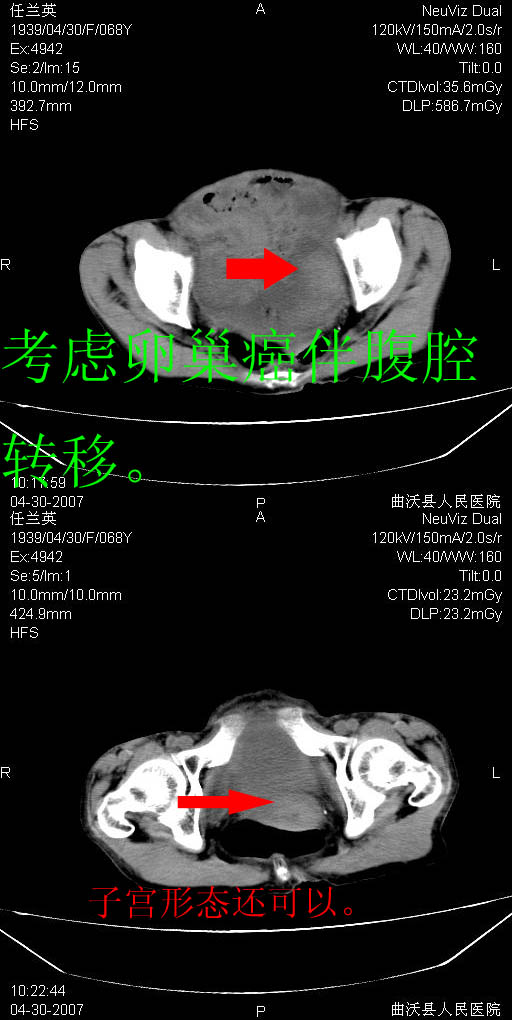

患者,女,68岁,感觉腹部憋涨发硬数天,查b超发现左盆腔有囊性肿物和少量腹水,行ct检查

1.考虑卵巢肿瘤并腹腔广泛性转移可能性大;

2.腹盆腔少量积液。

支持左侧卵巢恶性肿瘤伴网膜、腹膜广泛转移。

支持:左侧卵巢恶性肿瘤伴网膜、腹膜 腹膜后(淋巴结)广泛转移。

网膜、腹膜广泛转移考虑来源于左侧卵巢癌可能性大。不除外来源于消化系的肿瘤。

支持卵巢恶性肿瘤腹膜.肠系膜.淋巴结转移,

难的一见 典型 - 网膜饼  冰冻骨盆 可以当教学片了